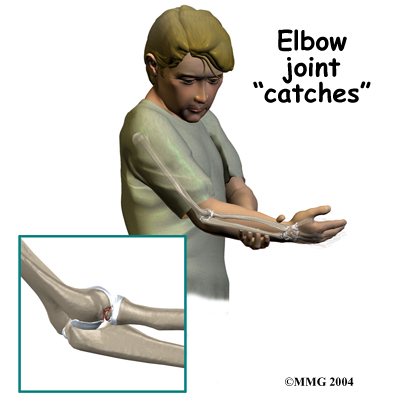

In advanced cases of elbow OCD, the patient may notice that the joint grinds (called crepitus). The elbow may also catch or lock up occasionally. These sensations may mean that a loose body is floating around inside the elbow joint. The joint may also feel warm and swollen, and the muscles around the elbow may appear to have shrunk in size (atrophied).